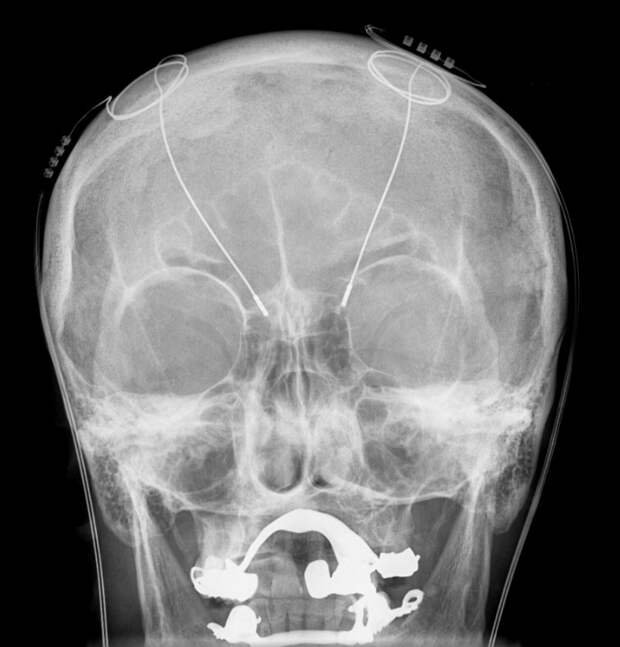

Электроды DBS на рентгене

Пациентке Дениз Бэкон, 65-летнему логопеду на пенсии, диагноз «болезнь Паркинсона» был поставлен 11 лет назад, в 2014 году. В случае Дениз заболевание проявлялось в виде брадикинезии (замедленных движений) и мышечной ригидности – повышенном тонусе мышц, затрудняющем их нормальную работу. Такие симптомы обычно хорошо купируются при помощи DBS, однако для успеха операции нужно очень точно «попасть» электродами в нужную зону и настроить режим стимуляции.

Точной настройке электродов помогает проведение операции с пробуждением: первый этап, в ходе которого в черепе проделывают небольшое отверстие и вводят электроды при помощи стереотаксической рамки, проводится под общим наркозом, а затем пациента пробуждают и смотрят за эффектом от стимуляции и финального позиционирования электродов.

В случае с Бэкон врачам из больницы Лондонского королевского колледжа было несколько легче – Дениз играла на кларнете, а что может быть точнее, чем мелкая моторика пальцев музыканта? Бригада нейрохирургов под руководством Кеюмарса Ашкана провела двустороннюю операцию в течение четырех часов. После вмешательства игра Дениз стала более четкой и плавной, а движения – более естественными.